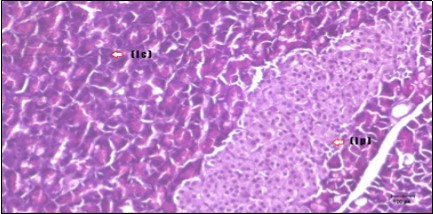

Figure 12.Photomicrogragh of pancreas section of treated rat with both Fenugreek and Glimepiride showing nearly normal islets of Langerhans with spindle (arrow) & polygonal cells (dashed- arrow). (H&E) (40x).

Photomicrogragh of pancreas section of treated rat with both Fenugreek and Glimepiride showing nearly normal islets of Langerhans with spindle (arrow) & polygonal cells (dashed- arrow). (H&E) (40x).

Histopathological observation in diabetic control showed degenerative changes in both endocrine and exocrine pancreases. A probable explanation may be related to oxidative stress resulting from hyperglycemia which decreases the antioxidants levels and increases ROS 33 and the activities of antioxidant enzyme were altered in diabetic rats. These effects further exacerbate the development and progression of diabetes complications and these may represent the causes of degeneration revealed in histological sections. Fenugreek improved blood glucose levels and insulin, lowered pancreatic islet and β-cells damage which may be attributed to its immune modulatory activity and insulin stimulation action along with its antioxidant potential 32. Glimepiride caused restoration of morphology of beta cell of diabetic and it increased percentage of beta cells 34. This protective effect could be attributed to the antioxidant properties of Glimepiride. Combination therapy improves the protective effect of both therapies alone.